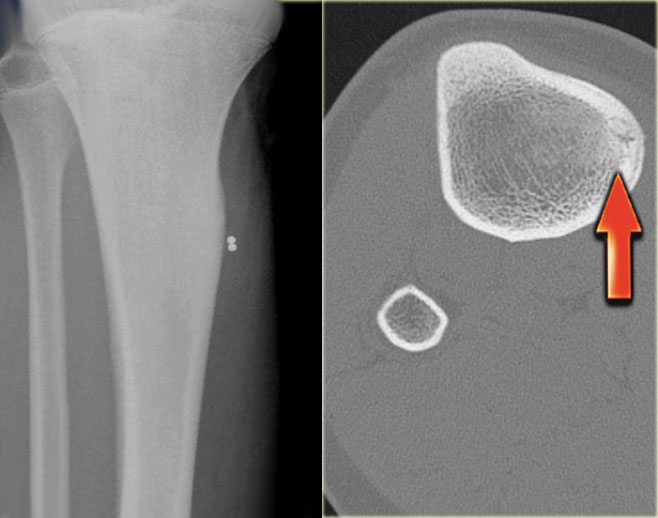

Here images of a 30-year-old male.

There is a wel-defined lytic lesion of the olecranon with several ridges and a pathologic fracture.

The differential diagnosis includes giant cell tumor and ABC.

The T2WI+FS shows fluid-levels due to sedimentation making ABC the most likely diagnosis.

Biopsy however revealed Brown tumor.